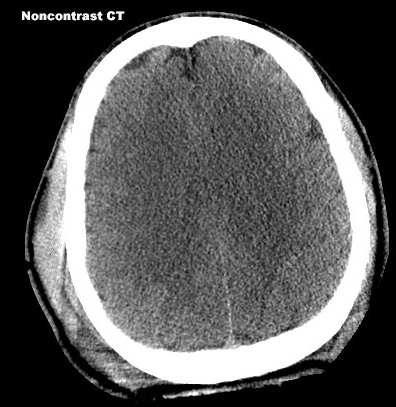

Diffuse Brain Edema

Findings: Absence of sulcal markings and poor differentiation of white and grey matter.